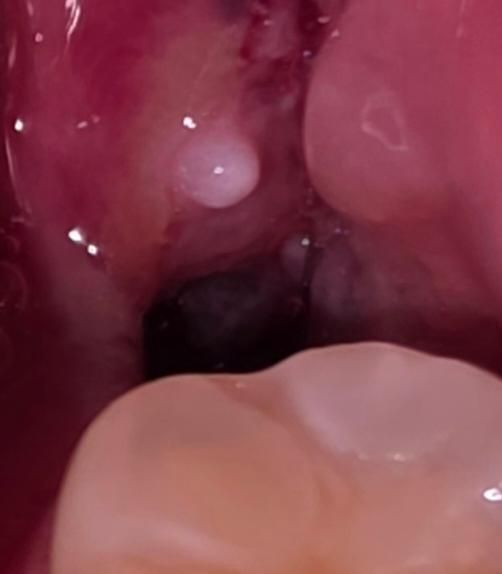

사랑니 발치 2일차인데 드라이소켓인가요?

치과에서 하지 말라는건 하지 않고 있고, 지금은 살짝 따끔거리며 심한 구취는 없습니다.

인터넷에 보이는 혈병의 모습이 없고 비어있는것 같이 보여서 걱정되어 질문합니다.

• 1번 째 사진

지금으로써는 드라이소켓 여부는 알 수 없습니다만 비어보이는거 자체를 걱정하진 않아도 됩니다 드라이소켓은 보통 3~5일차에 생깁니다